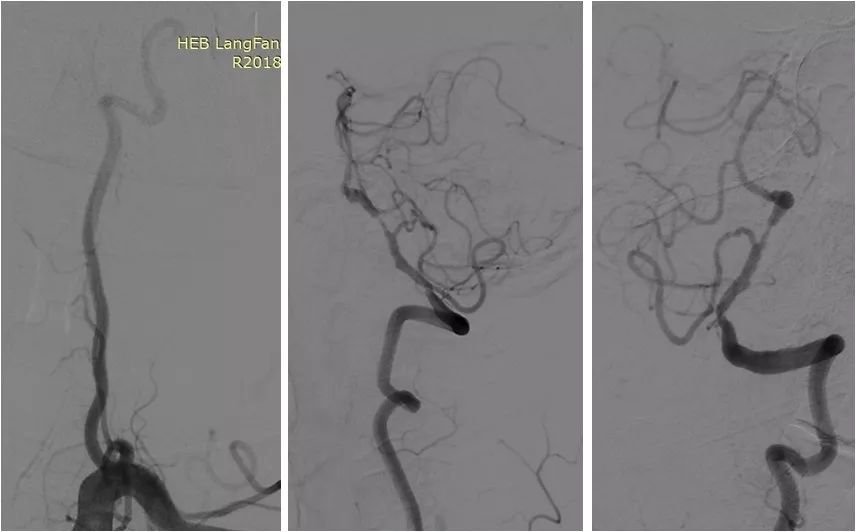

DSA:右颈内动脉C6段重度狭窄;双侧胚胎型大脑后动脉;左椎动脉V1段迂曲,V4段重度狭窄;右椎动脉纤细,V4段以远显影欠佳(图3-6)。

图3

图4

图5

图6